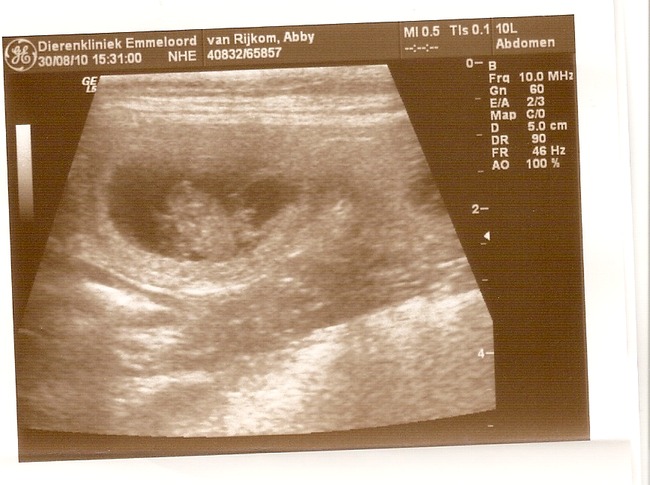

Onze vermoedens zijn bevestigd, Abby is inderdaad drachtig! En hoe...

Op de echo waren 7 levende pups met mooie kloppende hartjes te zien!!!

Hier trouwens de echo foto's:

Oh beetje een kleine foto... Ik zal kijken of ik 'm groter kan plaatsen

We zeiden ook al bij 5 jullie mogen nu wel stoppen hoor maar het ging maar door en door, we hebben allemaal echt iets van 3x getelt en steeds kwamen we op die schrikbarende 7 pups uit

Ja het blijft afwachten, ze kunnen altijd een foutje maken bij zo een echo. Maar heb meegeteld en er ook 7 gezien dus zal spannend worden